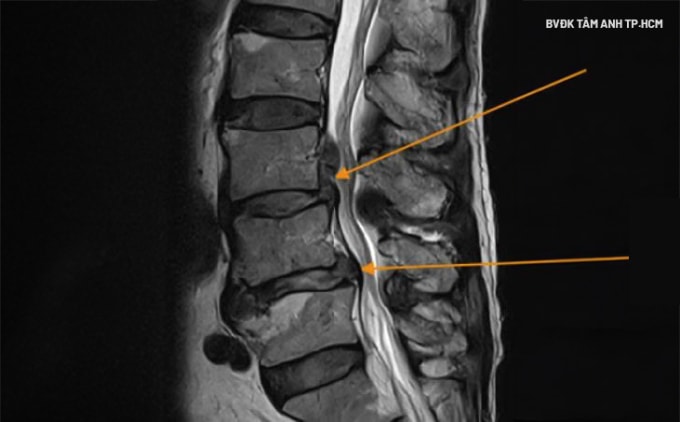

Anh Duy đến Bệnh viện Đa khoa Tâm Anh TP HCM khám trong tình trạng đau lan xuống chân, tê bì, đi lại khó khăn. Kết quả chụp MRI phát hiện thoát vị đĩa đệm cột sống lưng L3L4 và L4L5.